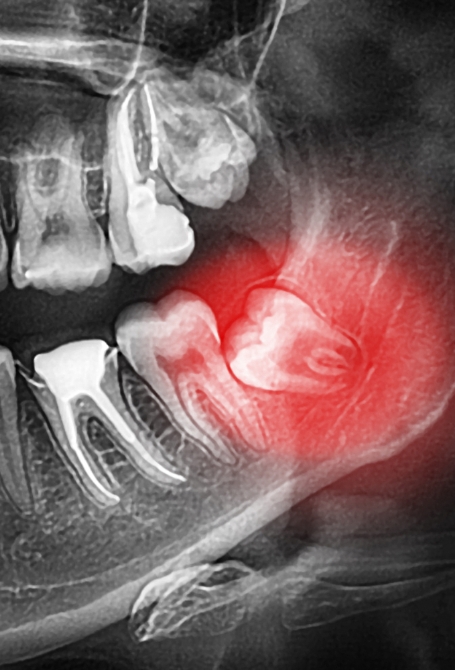

Nous proposons des soins adaptés pour traiter les dents et les tissus mous affectés par des maladies de divers degrés. Carie plus ou moins profonde, gingivite, parodontite, abcès : nous saurons enrayer la pathologie et traiter ses conséquences, au besoin.